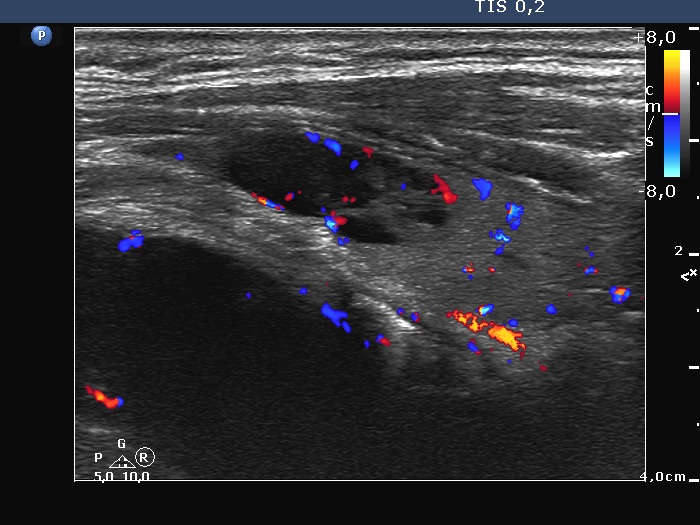

Thyroid cancers - case 1167 (ultrasonographic picture 8)

Left lobe, longitudinal scan, color Doppler mode. The vascularity is identical in the hypoechoic lesion to the nonlesional part of the lobe.